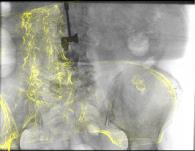

Deep Learning-based 2D/3D registration methods are highly robust but often lack the necessary registration accuracy for clinical application. A refinement step using the classical optimization-based 2D/3D registration method applied in combination with Deep Learning-based techniques can provide the required accuracy. However, it also increases the runtime. In this work, we propose a novel Deep Learning driven 2D/3D registration framework that can be used end-to-end for iterative registration tasks without relying on any further refinement step. We accomplish this by learning the update step of the 2D/3D registration framework using Point-to-Plane Correspondences. The update step is learned using iterative residual refinement-based optical flow estimation, in combination with the Point-to-Plane correspondence solver embedded as a known operator. Our proposed method achieves an average runtime of around 8s, a mean re-projection distance error of 0.60 $\pm$ 0.40 mm with a success ratio of 97 percent and a capture range of 60 mm. The combination of high registration accuracy, high robustness, and fast runtime makes our solution ideal for clinical applications.